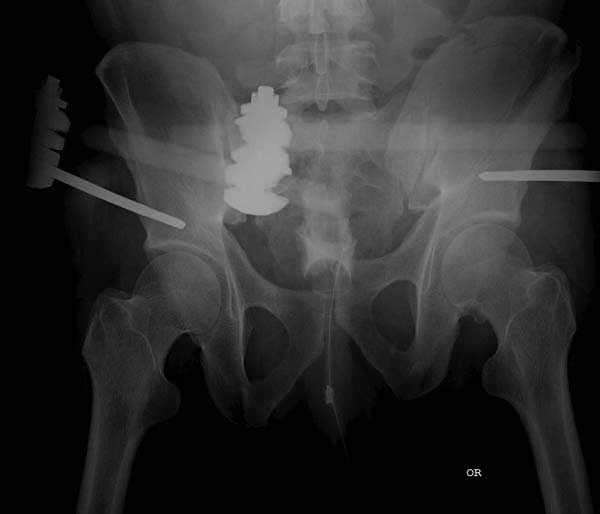

Здесь представлен случай 38 летнего больного (падение с высоты 9 метров) с нарушением тазового кольца. При поступлении для стабилизации передне-нижний аппарат наружной фиксации и на 6й день, вчера, операция из двух доступов.

Наружные фиксаторы создают не только стабильность костей таза, а также в экстренных случаях помогают уменьшить обьем таза в профилактике кровотечения!

Представлены снимки техники проведения стержней. Через место прикрепления прямой мышцы в Inferior Iliac Spine в направления вырезки создается жесткость. Weber clamp изнутри таза для репозиции, и фиксация после репозиции перелома крыла подвздошной кости. Наружный аппарат удален, нагрузка предполагается через два месяца.